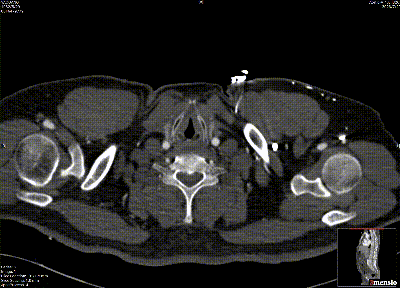

★ Case 5

男性,79岁,胸痛10+天

既往史:既往诊断高血压,未规律服药及监测血压

个人史:吸烟40余年,日均20支

头颈部CTA提示:颅内大脑后动脉P2段重度狭窄

夹层动脉瘤CTA:升主动脉局限性夹层、主动脉壁内血肿合并穿透性溃疡

术前影像

主动脉造影后,降主动脉限制支架置入,导入近端主体支架

升主动脉后造影定位后,释放近端主体支架,术毕造影

术后复查

First In Man早期结果